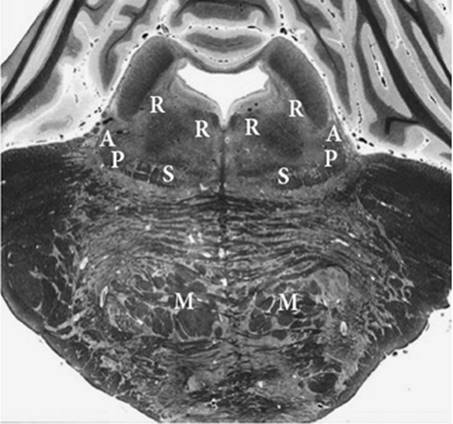

Figure 27.8. Section of the brainstem through the midpons. Note the relatively limited and separated territory of the brainstem actually monitored by evoked responses at this level. Function of the surrounding brain stem is assumed to be reflected by auditory and somatosensory function. Vital pathways and structures are near both the auditory and somatosensory pathways. A, auditory pathway; P, pain pathway; S, somatosensory pathway; R, reticular formation; M, descending motor pathway.

Figure 27.8 shows the somatosensory pathway schematically, together with the auditory pathway and nearby brainstem, midbrain, and cortical structures in a single slice through the pons. As shown in the figure, the auditory and somatosensory pathways are separated far enough to include multiple important structures in the territory between them. The anatomic locations of the two separated pathways explain why neurologic outcome is usually better when both evoked response modalities show a normal response. The presence of cortical responses to a peripheral stimulus indicates that the involved subcortical nervous pathway is intact and that cortical neurons are still functional to be activated and produce a measurable electrical response, both of which are necessary for a good long-term neurologic outcome.